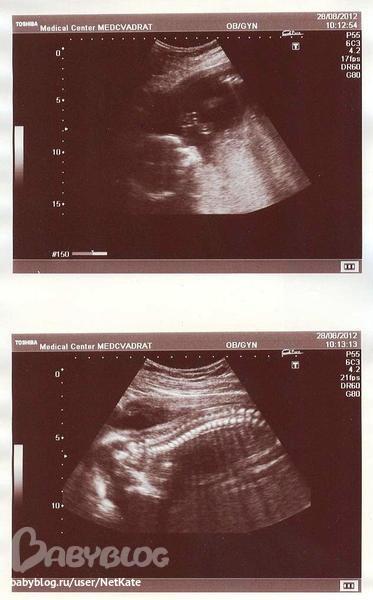

Наша егоза легла кверху спинкой и попкой, так что рассмотрели лишь отдельные части тела, а целиком , как раньше, уже не помещается в экран УЗИ-аппарата, и головкой вертела все время) Выкладываю пару снимков - головка в пол-оборота (щечки точно мои!), и позвоночник. Муж им особенно восторгался, на мой взгляд, похоже на рыбку))

Итак, наша малышка развивается как положено в срок, вес 520 грамм, не страдает нехваткой кислорода, обвития нет, предлежание головное (но все время вертится и может менять положение много раз), БПР 54 см, ОГ 199, ОЖ 181, ДБК 39, ДПК 37.

Все органы в норме, никаких отклонений или патологий не выявлено. Слава Богу! Со мной тоже все в порядке. Плацента расположена по задней стенке на 3 см выше внутреннего зева, сам зев закрыт, шейка матки без особенностей. Структура плаценты нормальная, воды в норме, пуповина имеет 3 сосуда.

Допплерометрия также без отклонений - "показатели гемодинамики в системе мать-плацента-плод в пределах нормативных значений". Ура! Сегодня по результатам УЗИ - к моей Г. Надеюсь, вес в норме, ужинаю настоем шиповника и яблочным пюре - муж натирает))